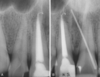

periapical abscess

periapical abscess